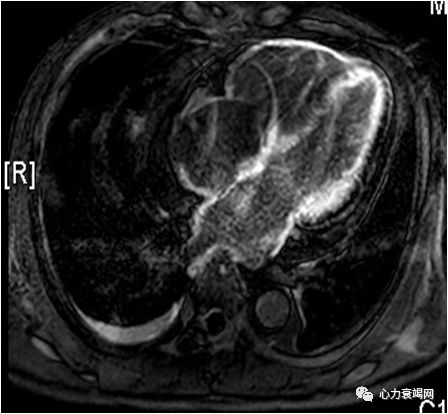

➤ 心脏MRI增强:心肌首过灌注可见心内膜下灌注减低,延迟扫描左、右心室可见弥漫性强化,以心内膜下强化为著。

➤ 心肌淀粉样变性,左室收缩及舒张运动减弱;少量心包积液;右侧中量胸腔积液,左侧少量胸腔积液。